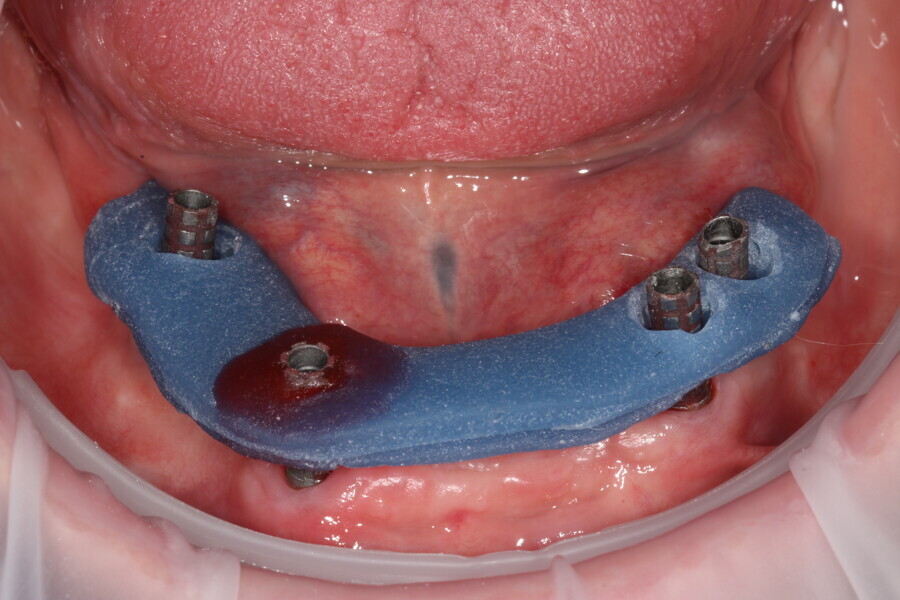

Fig. 15: Verification jig locked in situ to gain implant passivity.